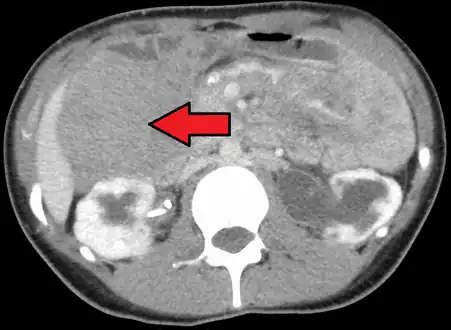

| Desmoid tumor as seen on CT scan | |

Aggressive fibromatosis or desmoid tumor is a rare condition. Desmoid tumors arise from cells called fibroblasts, which are found throughout the body and provide structural support, protection to the vital organs, and play a critical role in wound healing. These tumors tend to occur in women in their thirties, but can occur in anyone at any age. They can be either relatively slow-growing or malignant. However, aggressive fibromatosis is locally aggressive and can cause life-threatening problems or even death when they compress vital organs such as intestines, kidneys, lungs, blood vessels, or nerves. Most cases are sporadic, but some are associated with familial adenomatous polyposis (FAP). Approximately 10% of individuals with Gardner's syndrome, a type of FAP with extracolonic features, have desmoid tumors.[1]

Desmoid tumors may be classified as extra-abdominal, abdominal wall, or intra-abdominal (the last is more common in patients with FAP). It is thought that the lesions may develop in relation to estrogen levels or trauma/operations.